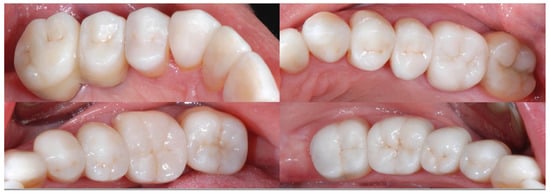

2.2. Clinical Example

2.3. Outcome Achieved